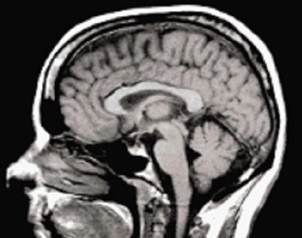

Con el objetivo de entender mejor enfermedades neurodegenerativas como el Alzhaimer, el banco de cerebros del Centro de Investigación y de Estudios avanzados (Cinvestav) se transformará en el Banco Nacional de Cerebros.

Con 35 encéfalos humanos de origen mexicano y más de 150 fragmentos de cerebros extranjeros, se buscarán terapias o fármacos que permitan combatir el alzheimer y otras alteraciones neuropatologías con estudios in-vitro.

Así mismo se crearán modelos celulares ahondar en la comprensión de las enfermedades neurodegenerativas, que son consecuencia de un mal funcionamiento de la proteína TAU pero que se procesan de modo similar al alzheimer pero no pueden ser tratadas del mismo modo.